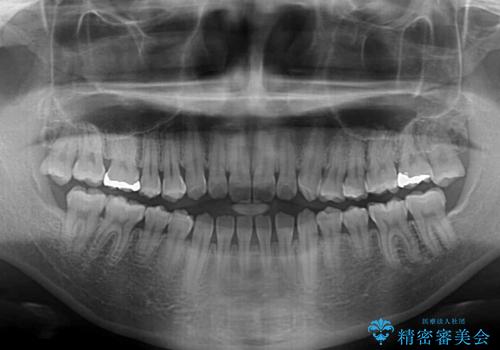

舌突出癖で口元が開いてしまう 舌トレーニングを行ったインビザライン矯正

- 前歯の上下スペースと前歯の隙間を気にして来院された患者様です。

上下の隙間に舌が入り込むことが、すきっ歯やオープンバイトの原因であったため、舌の筋肉のトレーニングも並行して行い、後戻りの抑制を図りました。